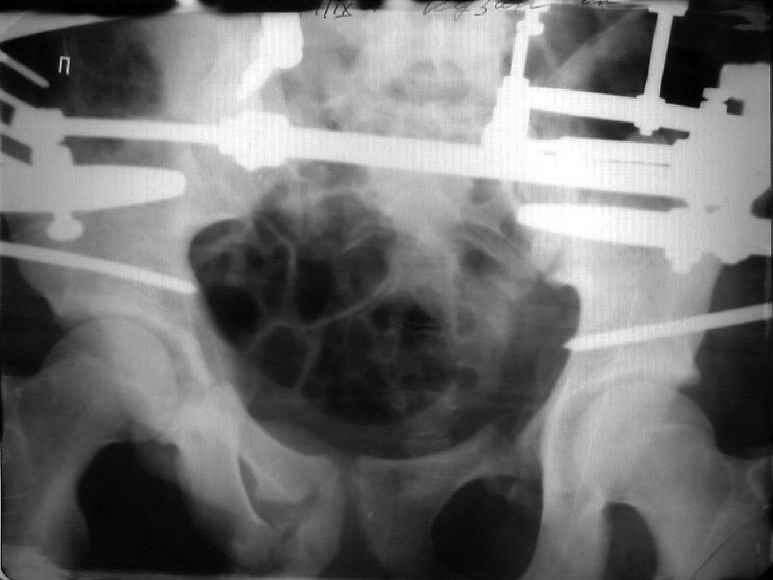

Застарелый перелом таза

Уважаемые коллеги! Хотел-бы обсудить варианты лечения больной с застарелым переломом таза. Возраст 40 лет. Травма 11 месяцев назад. Главный травматолог Камчатского Военно-морского госпиталя Юрий Алексеевич Булахтин

У больного судя по всему вертикальная деформация таза. А каковы основные жалобы пациента и какие у него функциональные требования?

Для принятия решения об оперативном лечении и о его объеме, представляется целесообразным выполнение рентгенографии в проекции "inlet", а так же функциональных рентгенограмм стоя попеременно на правой и левой нижних конечностях (для определения нестабильности тазового кольца).